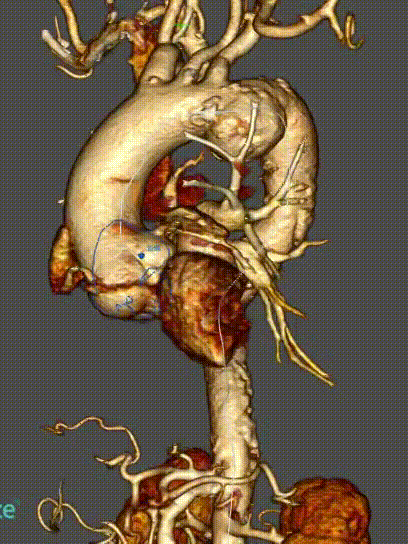

★ 病例5:解剖变异

(右位弓,迷走右锁骨下动脉)

释放方法和正常手术相同,但方向相反,需要调整。特别是分支的走向测试了该装置适应不同解剖结构的能力和便利性。

术后血管造影显示,所有分支方向与患者血管解剖结构匹配,尤其是无名动脉,外侧成近90°角,无内漏发生。随访显示所有分支通畅,无扭曲或迂曲,无卒中及内漏。